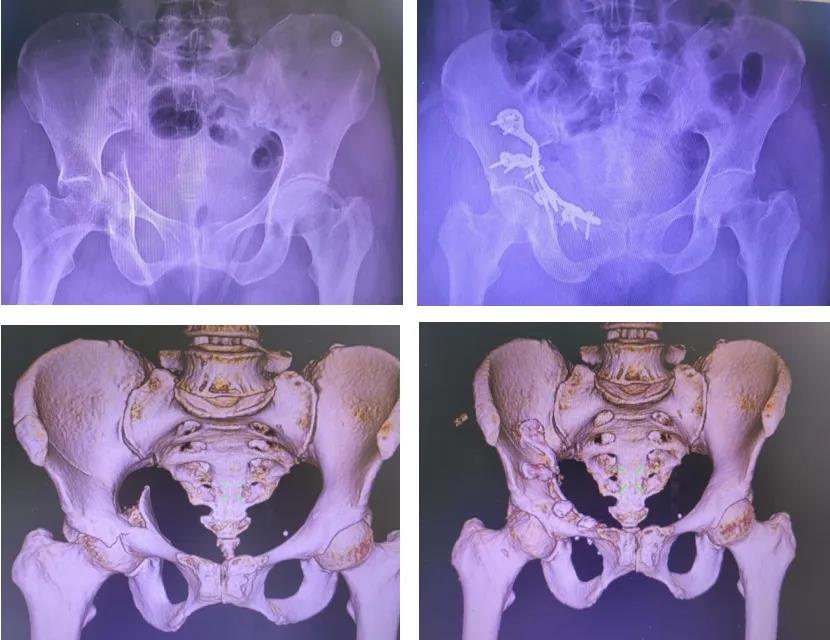

髋臼,作为连接躯干与下肢的“承重碗”,其解剖结构复杂、生物力学关键,直接决定着人体负重、行走与平衡功能。复杂髋臼骨折因其位置深在、骨折类型多变、毗邻重要神经血管结构,长期以来被视为创伤骨科领域最具挑战性的手术。

▲髋臼周围血管神经分布

抱着一线希望,韦阿姨慕名转诊至我院骨盆科。入院后,主管医师吕广桂迅速为她完成全面系统的检查评估,最终明确诊断:1. 右髋臼骨折(Letournel-Judet 分型 J 型,双柱);2. 骨盆骨折(Tile C1.1 型);3. 右髋关节中心脱位;4. 右股骨头骨折;5. 双侧多发肋骨骨折。

▲术前与术后影像学对比

微创手术带来的益处在术后即刻显现。由于肌肉软组织损伤极小,韦阿姨髋臼骨折处疼痛明显改善,疼痛评分显著低于传统手术患者,髋关节屈伸功能正常,可自主在床上翻身活动,饮食、精神状态等恢复较快,术后第3天便能在床上坐起,状态佳,气色好。复查骨盆X线和CT三维重建显示骨盆髋臼骨折复位固定良好。若后期康复训练到位,韦阿姨有望三个月后重新站立行走。